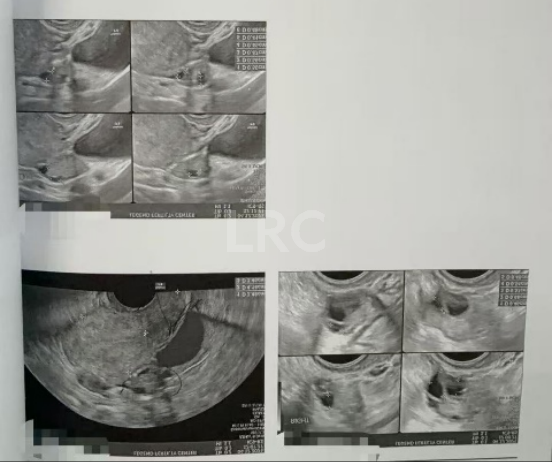

月经第二天 促排第一天

阴超检查:基础卵泡 10 颗

- 右侧卵泡 5 颗 (6,6,5,5,4mm)

- 左侧卵泡 5 颗 (5,5,5,5,4mm)

激素水平检查:

- 促卵泡生成素 2.50 miu/ml

- 促黄体生成素 8.40 miu/ml

- 雌二醇 22.70 pg/ml

- 泌乳素 14.10 ng/ml

促排第五天

阴超检查(只数能用卵子):

- 右侧可用卵泡 3 颗(8,7,5mm)

- 左侧可用卵泡 5 颗 (13,12,12,10,9,9,7mm)

- 促黄体生成素 10.00 miu/ml

子宫内膜厚度:6.7mm

促排第八天

阴超检查:

- 右侧卵泡 4 颗 (11,10,9,8mm)

- 左侧卵泡 7 颗 (20,18,18,16,15,12,12mm)

- 促黄体生成素 3.50 miu/ml

- 雌二醇 959.9 pg/ml

子宫内膜厚度:6.4mm

促排第九天

- 右侧卵泡 3 颗 (13,11,10mm)

- 左侧卵泡 7 颗 (22,22,20,20,17,13,13,12mm)

子宫内膜厚度:7.8 mm